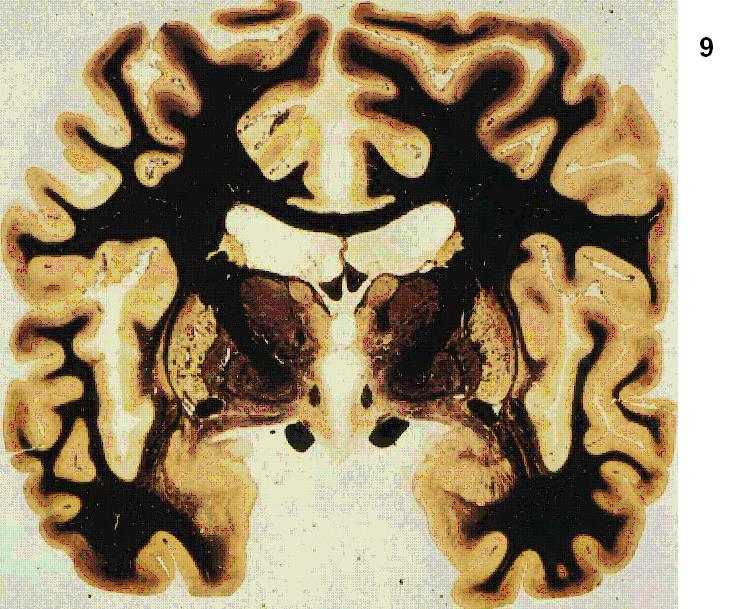

Figure 4 Figure 5 Figure 6 Figure 7 Figure 8 Figure 9 Figure 10 Figure 11